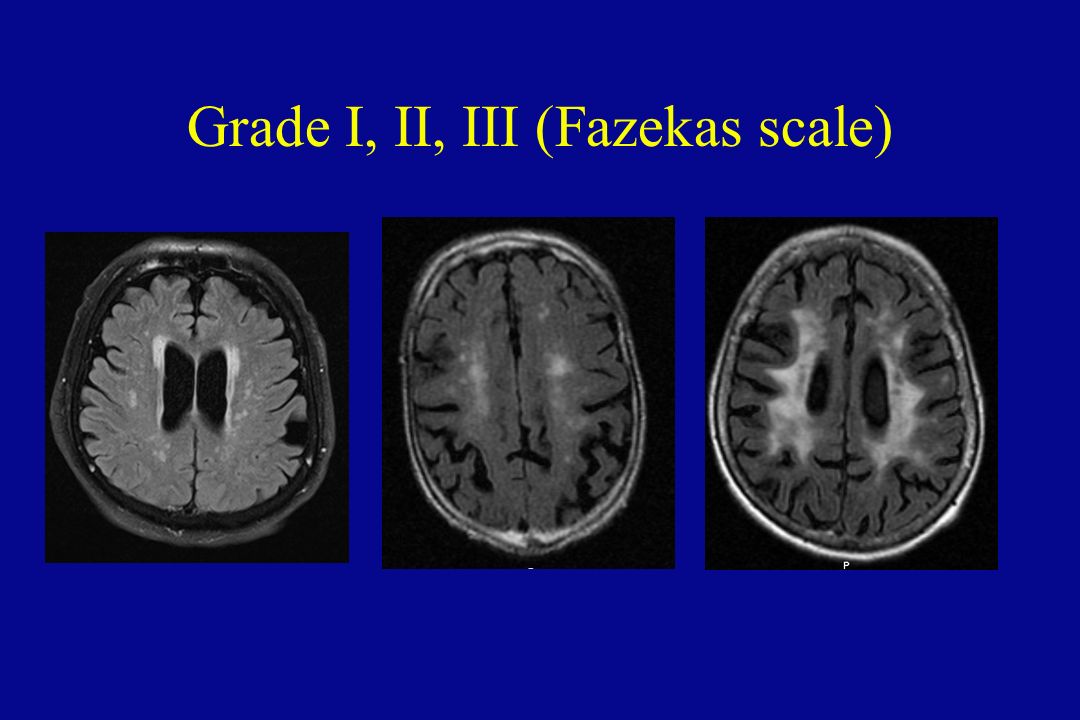

Fazekas grades

Fazekas grades. Dementia classification. Lesion traumtique cerebral classification.

Fazekas grades. Dementia classification. Lesion traumtique cerebral classification.